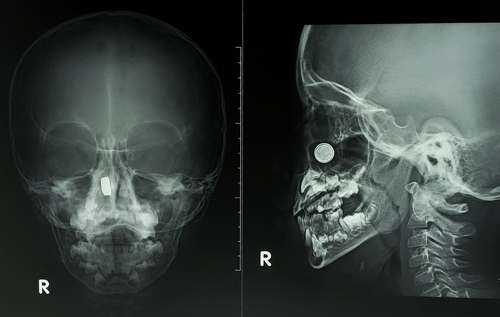

- Рентген носоглотки в боковой проекции. Голова слегка поворачивается, чтобы луч прошел сбоку. Такая проекция лучше всего показывает высоту носоглоточного свода, размеры аденоидов, степень перекрытия хоан, дает оценку просвета носоглотки. Именно боковая позиция помогает визуализировать те самые «тени», которые мешают воздуху проходить.

Расшифровка результатов

После снимка врач-рентгенолог готовит заключение. В описании рентгена носоглотки рентгенолог описывает, что именно показывает рентгенограмма, где видны отклонения и что требует внимания ЛОР-врача.

Что считается нормой:

- Просвет носоглоточного свода свободный, контуры ровные, патологических теней нет.

- Тени мягких тканей тонкие, симметричные; костные структуры четкие, без линий перелома.

- Придаточные пазухи прозрачны, уровней жидкости не определяется.

- Носовой ход не сужен, тени хоан свободны.

- Аденоидные разрастания. Утолщенная тень в своде носоглотки, перекрывающая просвет частично или значительно. По рентгенограмме судят о степени, врач сопоставляет с жалобами.

- Синусит. Уровень жидкости или диффузное «затемнение» в пазухах на фоне отека; на снимке по Уотерсу эту зону будет видно лучше.

- Искривление перегородки. Косвенные признаки — асимметрия носовой полости, смещение костных контуров.

- Травма. Линии перелома костей носа/скул/стенок синусов, подвывихи, участки смещения. В экстренной ситуации это помогает быстро отправить пациента к профильному специалисту.

- Опухолевые образования и кисты. Описывают как «объемные тени», уточняют границы и влияние на окружающие структуры; далее решают вопрос о КТ/МРТ.

- Гипертрофия мягких тканей. Утолщение в области носоглоточной миндалины, рыхлые тени вдоль задней стенки — косвенные признаки воспаления.

Важно понимать: рентген — базовый визуальный метод. Он отлично позволяет увидеть кости и «крупные» изменения мягких тканей, но не дает срезов, как КТ. Поэтому в сложных случаях врач дополнит диагностику другими исследованиями, чтобы оценить состояние в деталях.